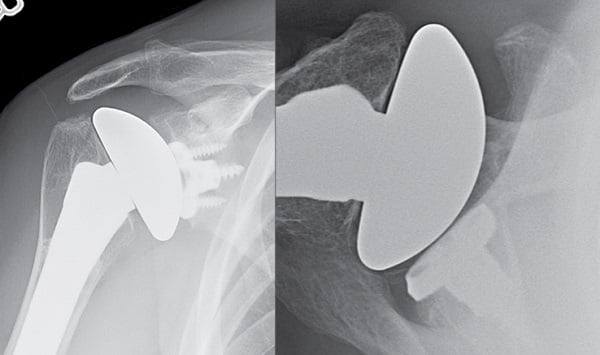

The patient had an excellent recovery. After immobilization in a sling for 4 weeks, he began progressive physical therapy to regain motion and strength. At the 4-year follow-up examination, his right shoulder demonstrated 170° of forward elevation, 60° of external rotation, and internal rotation to T8. His rotator cuff strength was 5/5. Radiographs showed that the right humeral head was well centered, the glenoid version was neutral, and the bone graft had incorporated on the posterior glenoid (Fig. 4).

Figure 4: AP (left) and axillary (right) radiographs at 4-year follow-up demonstrate right anatomic shoulder replacement with metal backed convertible glenoid, restoration of neutral glenoid version, and incorporation of the bone graft.